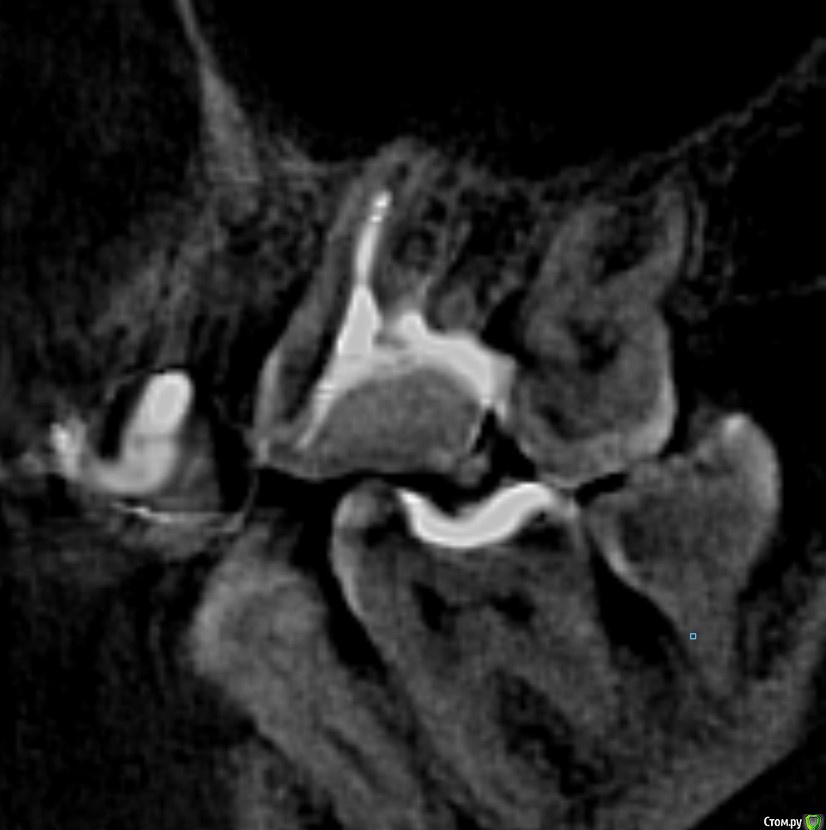

Александр9 Опубликовано 27 августа, 2020 Автор Поделиться Опубликовано 27 августа, 2020 На таком снимке вообще сложно что-то увидеть, но у этих зубов четвертый канал совсем не редкость. На КТ должно быть видно лучше. а зуб действительно надо перелечивать из-за канала? Поигрался с файлом КТ, не знаю, наглядна ли такая проекция. На таком снимке вообще сложно что-то увидеть, но у этих зубов четвертый канал совсем не редкость. На КТ должно быть видно лучше. Ссылка на комментарий